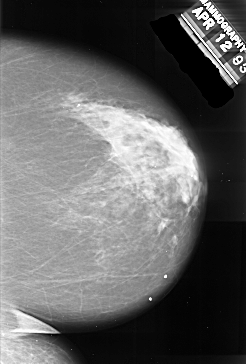

A_1017_1.LEFT_MLO

LEFT_MLO LINES 5866 PIXELS_PER_LINE 3466 BITS_PER_PIXEL 16 RESOLUTION 42 OVERLAY